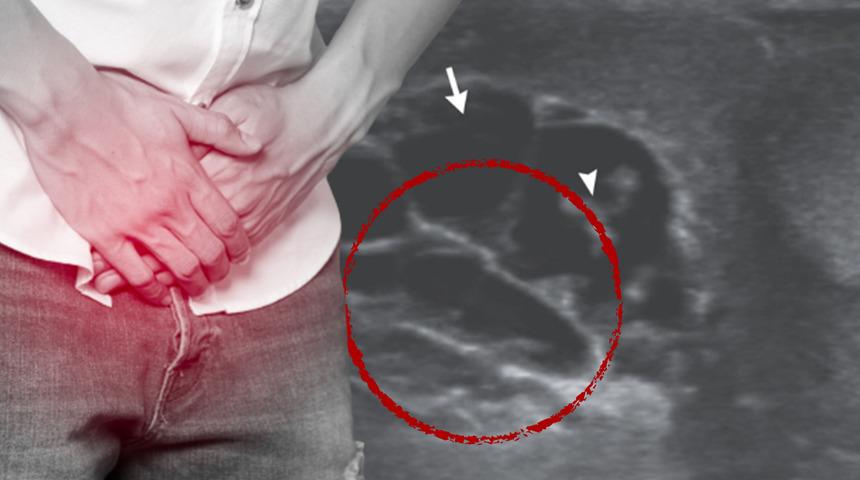

Hindistan’da yaşayan 26 yaşındaki ismi açıklanmayan bir adamın yaşadığı tıbbi rahatsızlık tıp tarihine geçti. Adamın sağ testine ait ultrason görüntülerinde ‘dans eden solucanlar’ internette kısa sürede gündem oldu. Testis torbasında ağrı, şişkinlik ve ateşle hastaneye başvuran adamın özel bölgesinde iplik benzeri solucanların olduğu ortaya çıktı. Raporda, solucanların Wuchereria bancrofti türünün sivrisinek yoluyla bulaşan nematodları (yuvarlak solucanlar) olduğu ifade edildi.

Sivrisinek yoluyla yerleşen ve tedavi edilmezse kan kanallarında altı ila sekiz yıla kadar yaşamayı başaran solucanların üreyebildikleri belirtildi. Tedavi altına alınan adamın üç haftalık yoğun ilaç tedavisinin sonrasında solucanlardan tamamen kurtulmayı başardı. Testis torbasında tedavinin sonucunda çekilen ultrason görüntüleri ise “parti bitti” diyerek gösterildi.